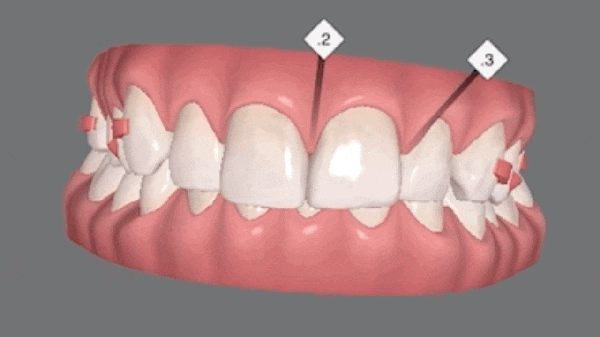

치아 사이즈 및 형태를 개선시키기 위하여 최소삭제(무삭제) 라미네이트와 2~3개월 안에 마무리 가능한 인비절라인 익스프레스 장치를 추천드렸습니다. 환자분께서는 짧은 기간 안에 본인의 치아에 크게 손을 대지 않고 치료가 가능한 인비절라인 익스프레스 장치를 선택하셨습니다.

아무래도 어렸을 때 치아교정을 하다가 힘들어서 본인이 중단한 적이 있기 때문에 오랜 기간이 걸리는 교정치료라면 선택을 하지 않으셨을텐데, 2~3개월이라는 비교적 짧은 기간 안에 티가 나지 않는 장치료 개선이 가능하다면 인비절라인으로 진행해보기를 원하셨습니다. 원래는 라미네이트 시술을 염두에 두고 내원하셨었는데, 처음 상담시 아무리 무삭제, 최소삭제라고 하더라도 라미네이트 치료에 약간의 부담감을 가지고 계셨었습니다. 그러나 짧은 기간 안에 본인이 원하는 부분만 간단하게도 치아 교정이 가능하다는 것을 이번 기회에 알게 되어서 너무 좋다고 하셨습니다.